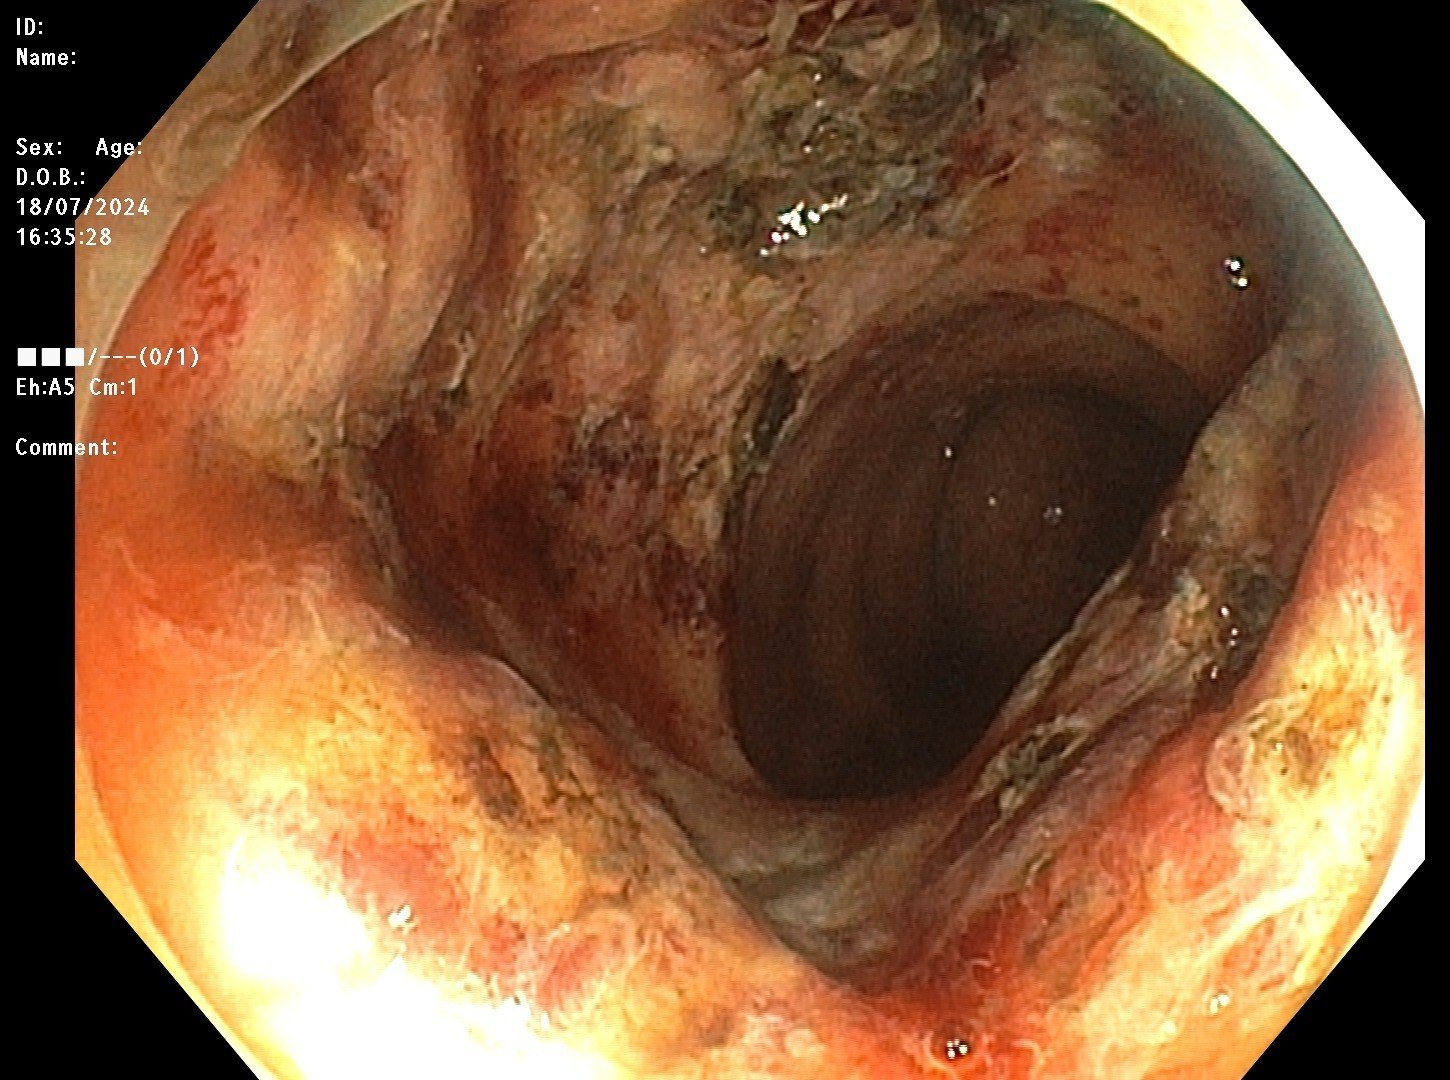

- Hình ảnh sau can thiệp cầm máu, đốt Argon Plasma

Theo BSCKI. Nguyễn Đăng Tuấn – Phó trưởng Khoa Tiêu hóa – Nội soi: Phương pháp cầm máu bằng Argon Plasma có ưu điểm là đông máu không tiếp xúc, sử dụng khí trơ argon phát ra tia plasma, phân bố năng lượng nhiệt lên các mô xung quanh đầu dò để xử lý tổn thương. Nhờ đó cải thiện tối ưu những tổn thương ở mạch máu, cầm máu nhanh, không gây đau đớn, giảm tai biến. Với bệnh nhân trên, xạ trị gây viêm trực tràng dẫn đến chảy máu; nếu người bệnh không được phát hiện và điều trị hiệu quả, có thể gây ra biến chứng nguy hiểm như thiếu máu cấp tính hoặc mạn tính và tử vong.

Ngay sau can thiệp, tình trạng xuất huyết tiêu hóa của người bệnh đã được kiểm soát, không còn chảy máu, người bệnh đã đại tiện phân vàng. Sức khỏe bệnh nhân dần hồi phục và được xuất viện.